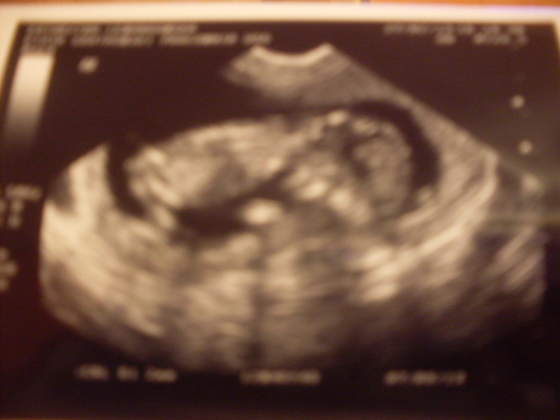

A orientujecie się czy musi być robione badanie usg przezierności karku itp? Można je sobie odpuścić? Chętnie bym zrezygnowała z tak długiego męczenia Maluszka i tak za często do niego zaglądam (jestem w 10tc i już 5 razy był podglądany - w przyszły wtorek będzie po raz 6).